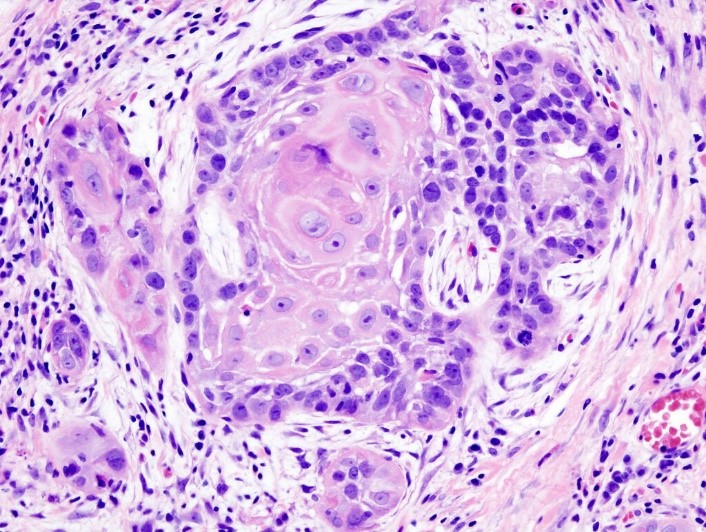

- Биопсия опухоли, гистологическое исследование (рис.2).

Рис.2 Гистологическое исследование. Плоскоклеточный рак